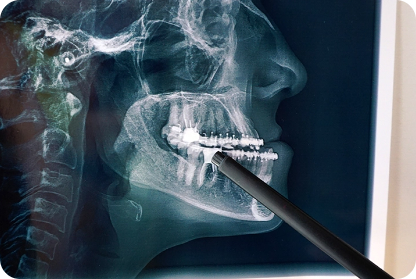

口腔外科

親知らずの抜歯や歯根端切除手術などに対応しています。

高難度のケースでも歯科用CTで診断し、安全かつ迅速に治療を行います。

歯科用CTや詳細な診断をもとに、原因に応じた適切な治療を行います。